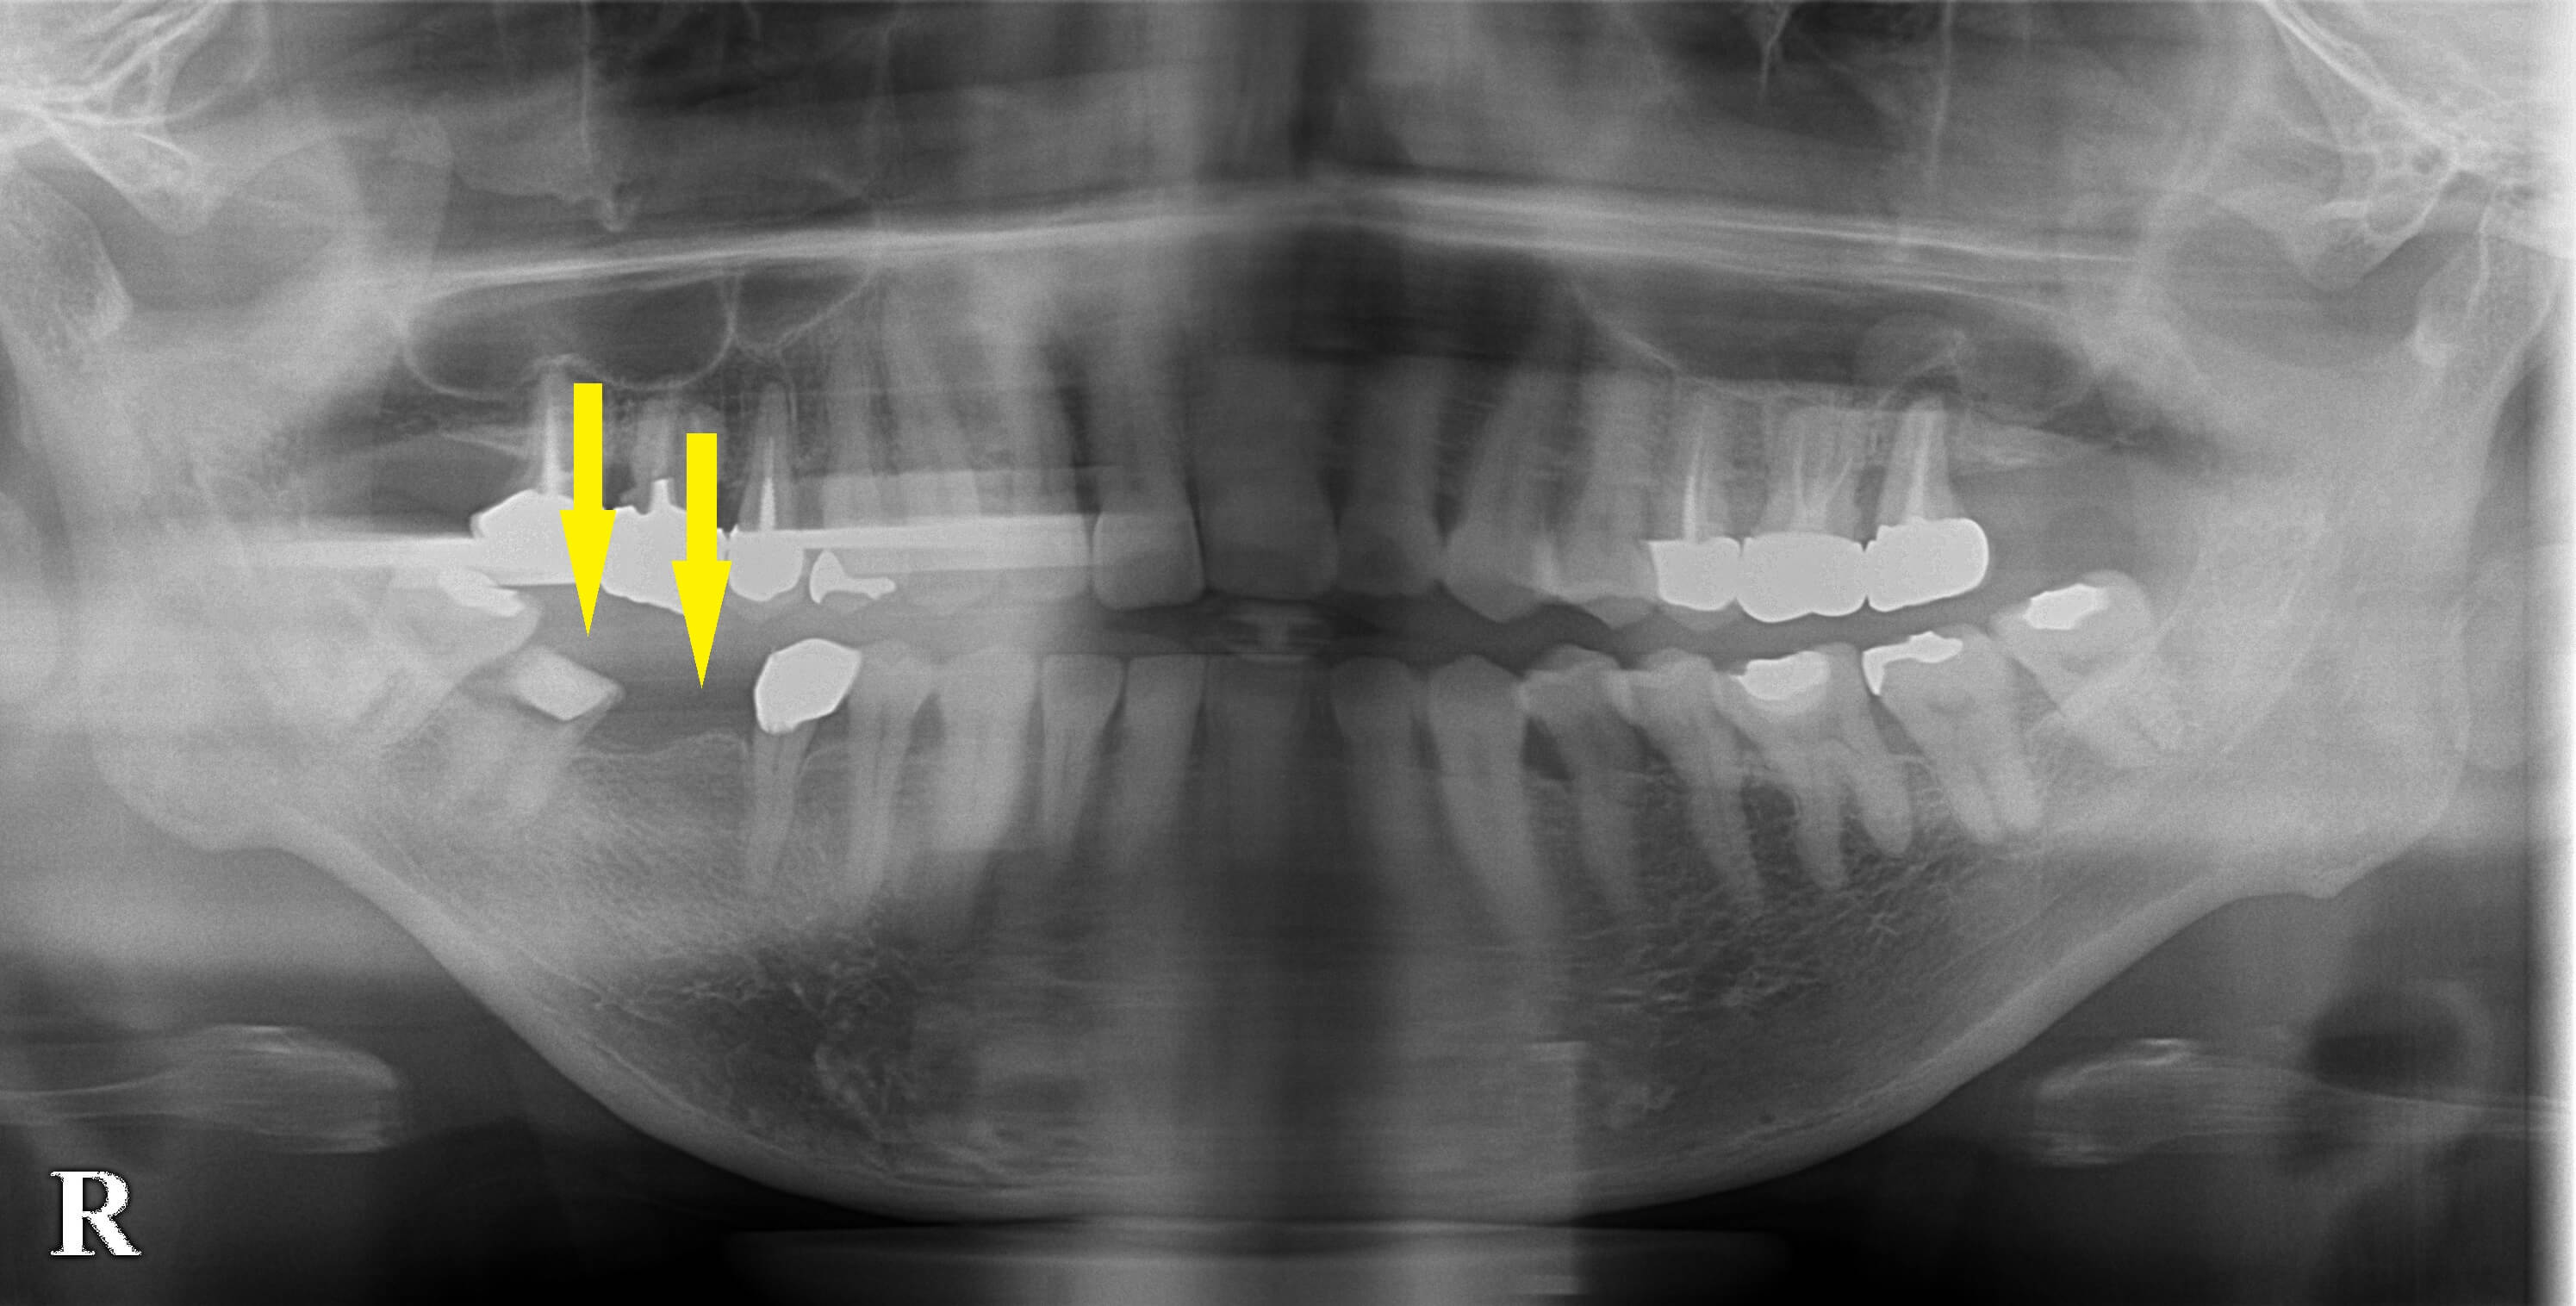

右下顎のブリッジが外れて、以前通院していた歯科医院に行ったところ、ブリッジの支えになっている歯が崩壊状態で残せないと説明されたそうです。

もう一度同じ設計のブリッジはできないので、ブリッジなら、4~5歯の連結になると言われたそうです。

ブリッジの支えになっていた、後方の歯を抜歯し、

治癒を待ってインプラントを2本埋入する計画で、同意がいただけました。

抜歯後、数か月待って、本日、2本のインプラント埋入術を行いました。